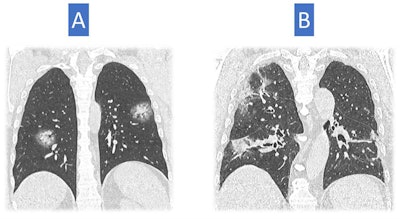

Image A shows larger opacities rounded in shape and some consolidation with a halo of ground glass. This sign has been described in COVID-19 cases. Consolidation is also present in image B, but the consolidation looks a bit different with architectural distortion, consistent with an organizing phase of COVID-19 pneumonia. These show a later stage of pneumonia than in the first three examples.He noted that CT scans may be helpful for very specific indications but stressed that it was risky to provide a single strict diagnostic flowchart. Patient diagnosis depends on the endemic environment, namely the pretest probability, and the internal resources of the hospital.